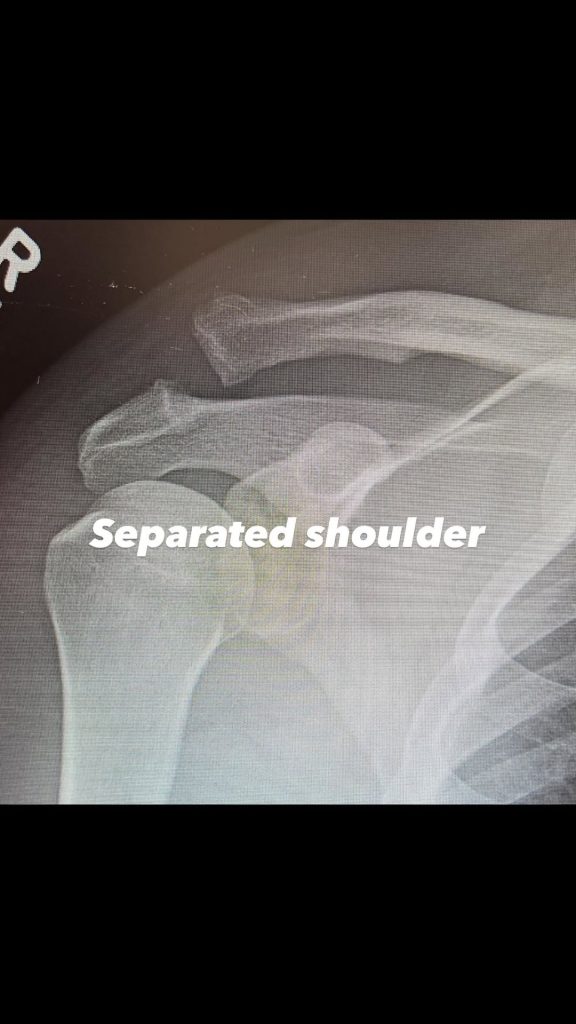

A través de redes sociales, el protagonista de Magic Mike compartió imágenes y un mensaje honesto sobre este momento físico complicado. Sin dramatizar, pero tampoco minimizando la situación, Tatum dejó claro que la lesión lo obligó a frenar, pasar por quirófano y replantearse su ritmo de vida, algo nada sencillo para alguien acostumbrado a la exigencia física constante.